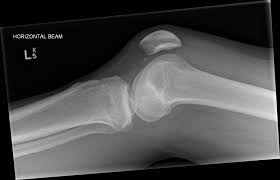

The radiographs demonstrated abnormal contour of the medial femoral condyle, consistent with an osteochondral defect, and a fabella posterior to the knee. Methods sixteen knees with a small medial femoral. It acts to support a significant amount of the patient's body weight. An imbalance of the muscles around the knee (some muscles are weaker than others.) overuse (repeated bending or twisting) of the knee joint, especially during sports. If there is a fracture (break) in part of the condyle, this is known as a fracture of the femoral condyle. The medial femoral condyle is supplied by a plexus of vessels from the descending genicular artery and the medial superior genicular artery. Damage may also be the result of a direct blow to the knee. Palpable to either side of the knee joint when it is bent, they are known specifically as the medial and lateral femoral condyles.

A bone fracture at this location is termed a femoral condyle fracture. Tendons and ligaments attach your kneecap to your shinbone and thigh. What is an articular cartilage defect and how is it treated? This is associated with a positive bone scan and, frequently, a radiolucent lesion in the subchondral zone. Damage may also be the result of a direct blow to the knee.